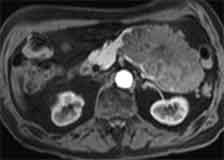

| axiale T1-gew. post KM FS |

axiale MIP | coronare T1-gew. post KM FS |

coronare MIP |